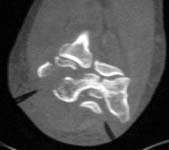

Images are of 59 yo female with low, comminuted distal humerus fx with fragments free posteriorly, high degree of comminution laterally plus involvement of the medial condyle.

Any thoughts re: management are appreciated. Approach to allow access and fixation medially as well as anterior & posterior. Total elbow arthroplasty ?

at 59 years old, i would opt for ORIF. i would use a posterior approach with olecranon osteotomy - double plating with plates perpendicular to each other - with the goal being anatomic restoration and stable fixation for early motion to minimize stiffness. It is hard to say more since I would want to see more of the radiographic studies for preoperative planning. (ie, at least the AP x-ray, and probably at least a few more of the CT images). From what I can see, i think the main fragments are large enough for stable fixation. If not, the fixation might need supplementation with one of the hinged external fixators. i think the large anterior fragment seen on the lateral view is the capitellum and it would have to be retrieved. i think it would be possible with the posterior approach, but that is where access to more imaging would be helpful.